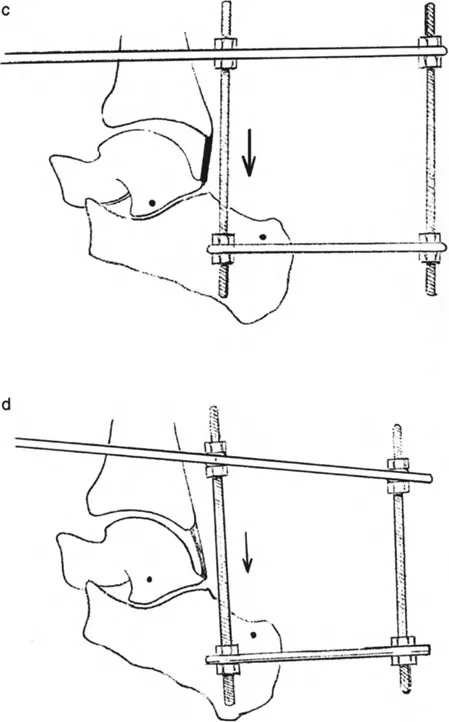

إزالة النتوءات العظمية وتعميق التلم الكاحلي

في حالات تقوس الكاحل الناتجة عن اصطدام عظمي (Bony Impingement) بسبب نتوءات عظمية في حافة الظنبوب الأمامية أو في التلم الظهري لعظم الكاحل، يقوم الأستاذ الدكتور محمد هطيف بإزالة هذه النتوءات وتعميق التلم الكاحلي للسماح لعظم الكاحل بالثني للأعلى بحرية.

* صورة توضح النتوءات العظمية التي تسبب اصطدامًا في الكاحل.

قطع العظم التصحيحي (Osteotomy)

عند وجود تشوهات عظمية مثل تقوس الظنبوب البعيد، قد يتطلب الأمر قطع العظم وإعادة توجيهه. على سبيل المثال، يمكن إجراء قطع عظم قبة ظهرية (Dorsiflexion focal dome osteotomy) في الظنبوب البعيد لتصحيح انحنائه.